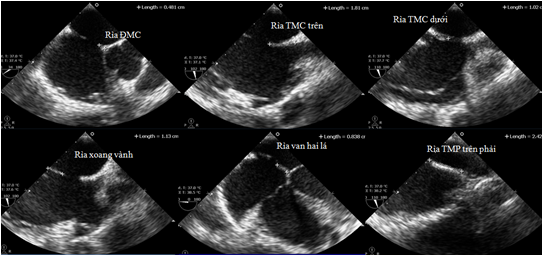

Siêu âm tim qua thành ngực

• Bệnh lý van tim: hẹp, hở van tim. Khảo sát, đánh giá sự thay đổi cấu trúc các lá van tim, đóng không kín, mở hạn chế, đánh giá hoạt động của van tim nhân tạo trên người bệnh thay van tim.

• Khảo sát các buồng tim: sự dày thành tim, giãn buồng tim, đánh giá hệ quả của tăng huyết áp hay các bệnh lý làm thay đổi kích thước các buồng tim, huyết khối, u nhầy buồng tim.

• Bệnh lý cơ tim: khảo sát đánh giá sự vận động các thành tim giúp chẩn đoán trong bệnh lý nhồi máu cơ tim, bệnh cơ tim phì đại, giãn nở.

• Dị tật tim bẩm sinh: tầm soát bệnh lý tim bẩm sinh từ bào thai đến trưởng thành như thông liên thất, thông liên nhĩ, còn ống động mạch, tứ chứng Fallot.

• Theo dõi huyết động trên người bệnh hồi sức: đánh giá cung lượng tim, sức co bóp cơ tim, áp lực động mạch phổi, tràn dịch màng ngoài tim, đáp ứng bù dịch.

• Theo dõi sau can thiệp tim mạch: đánh giá vị trí của dụng cụ trong can thiệp các bệnh lý tim bẩm sinh, cấy máy tạo nhịp.